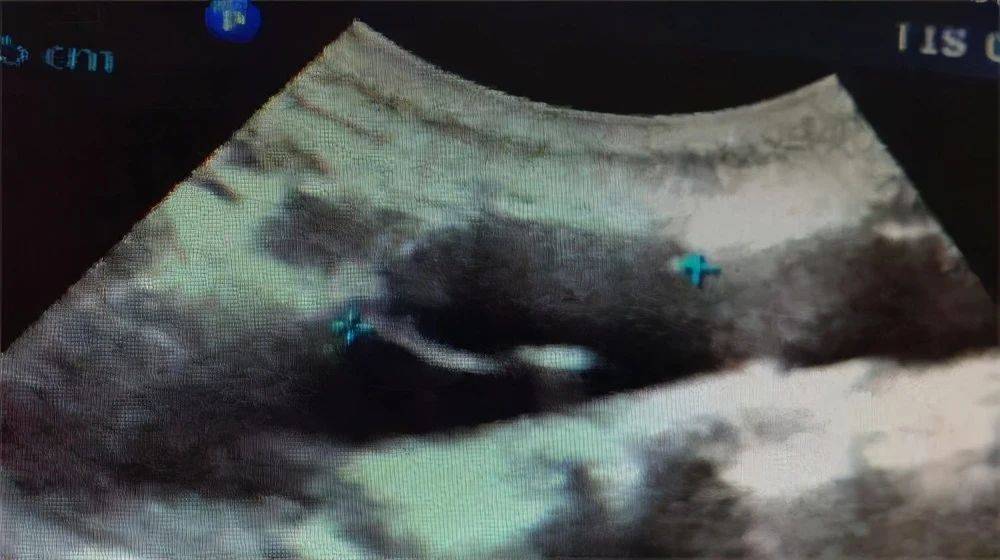

腹主动脉长轴切面 , 腔内局部可见膜样强回声 。 夹层动脉瘤内可见真腔和假腔 , 真假腔的鉴别要注意几点:

腹主动脉长轴切面 , 腔内可见膜样强回声 , 呈双腔征 。